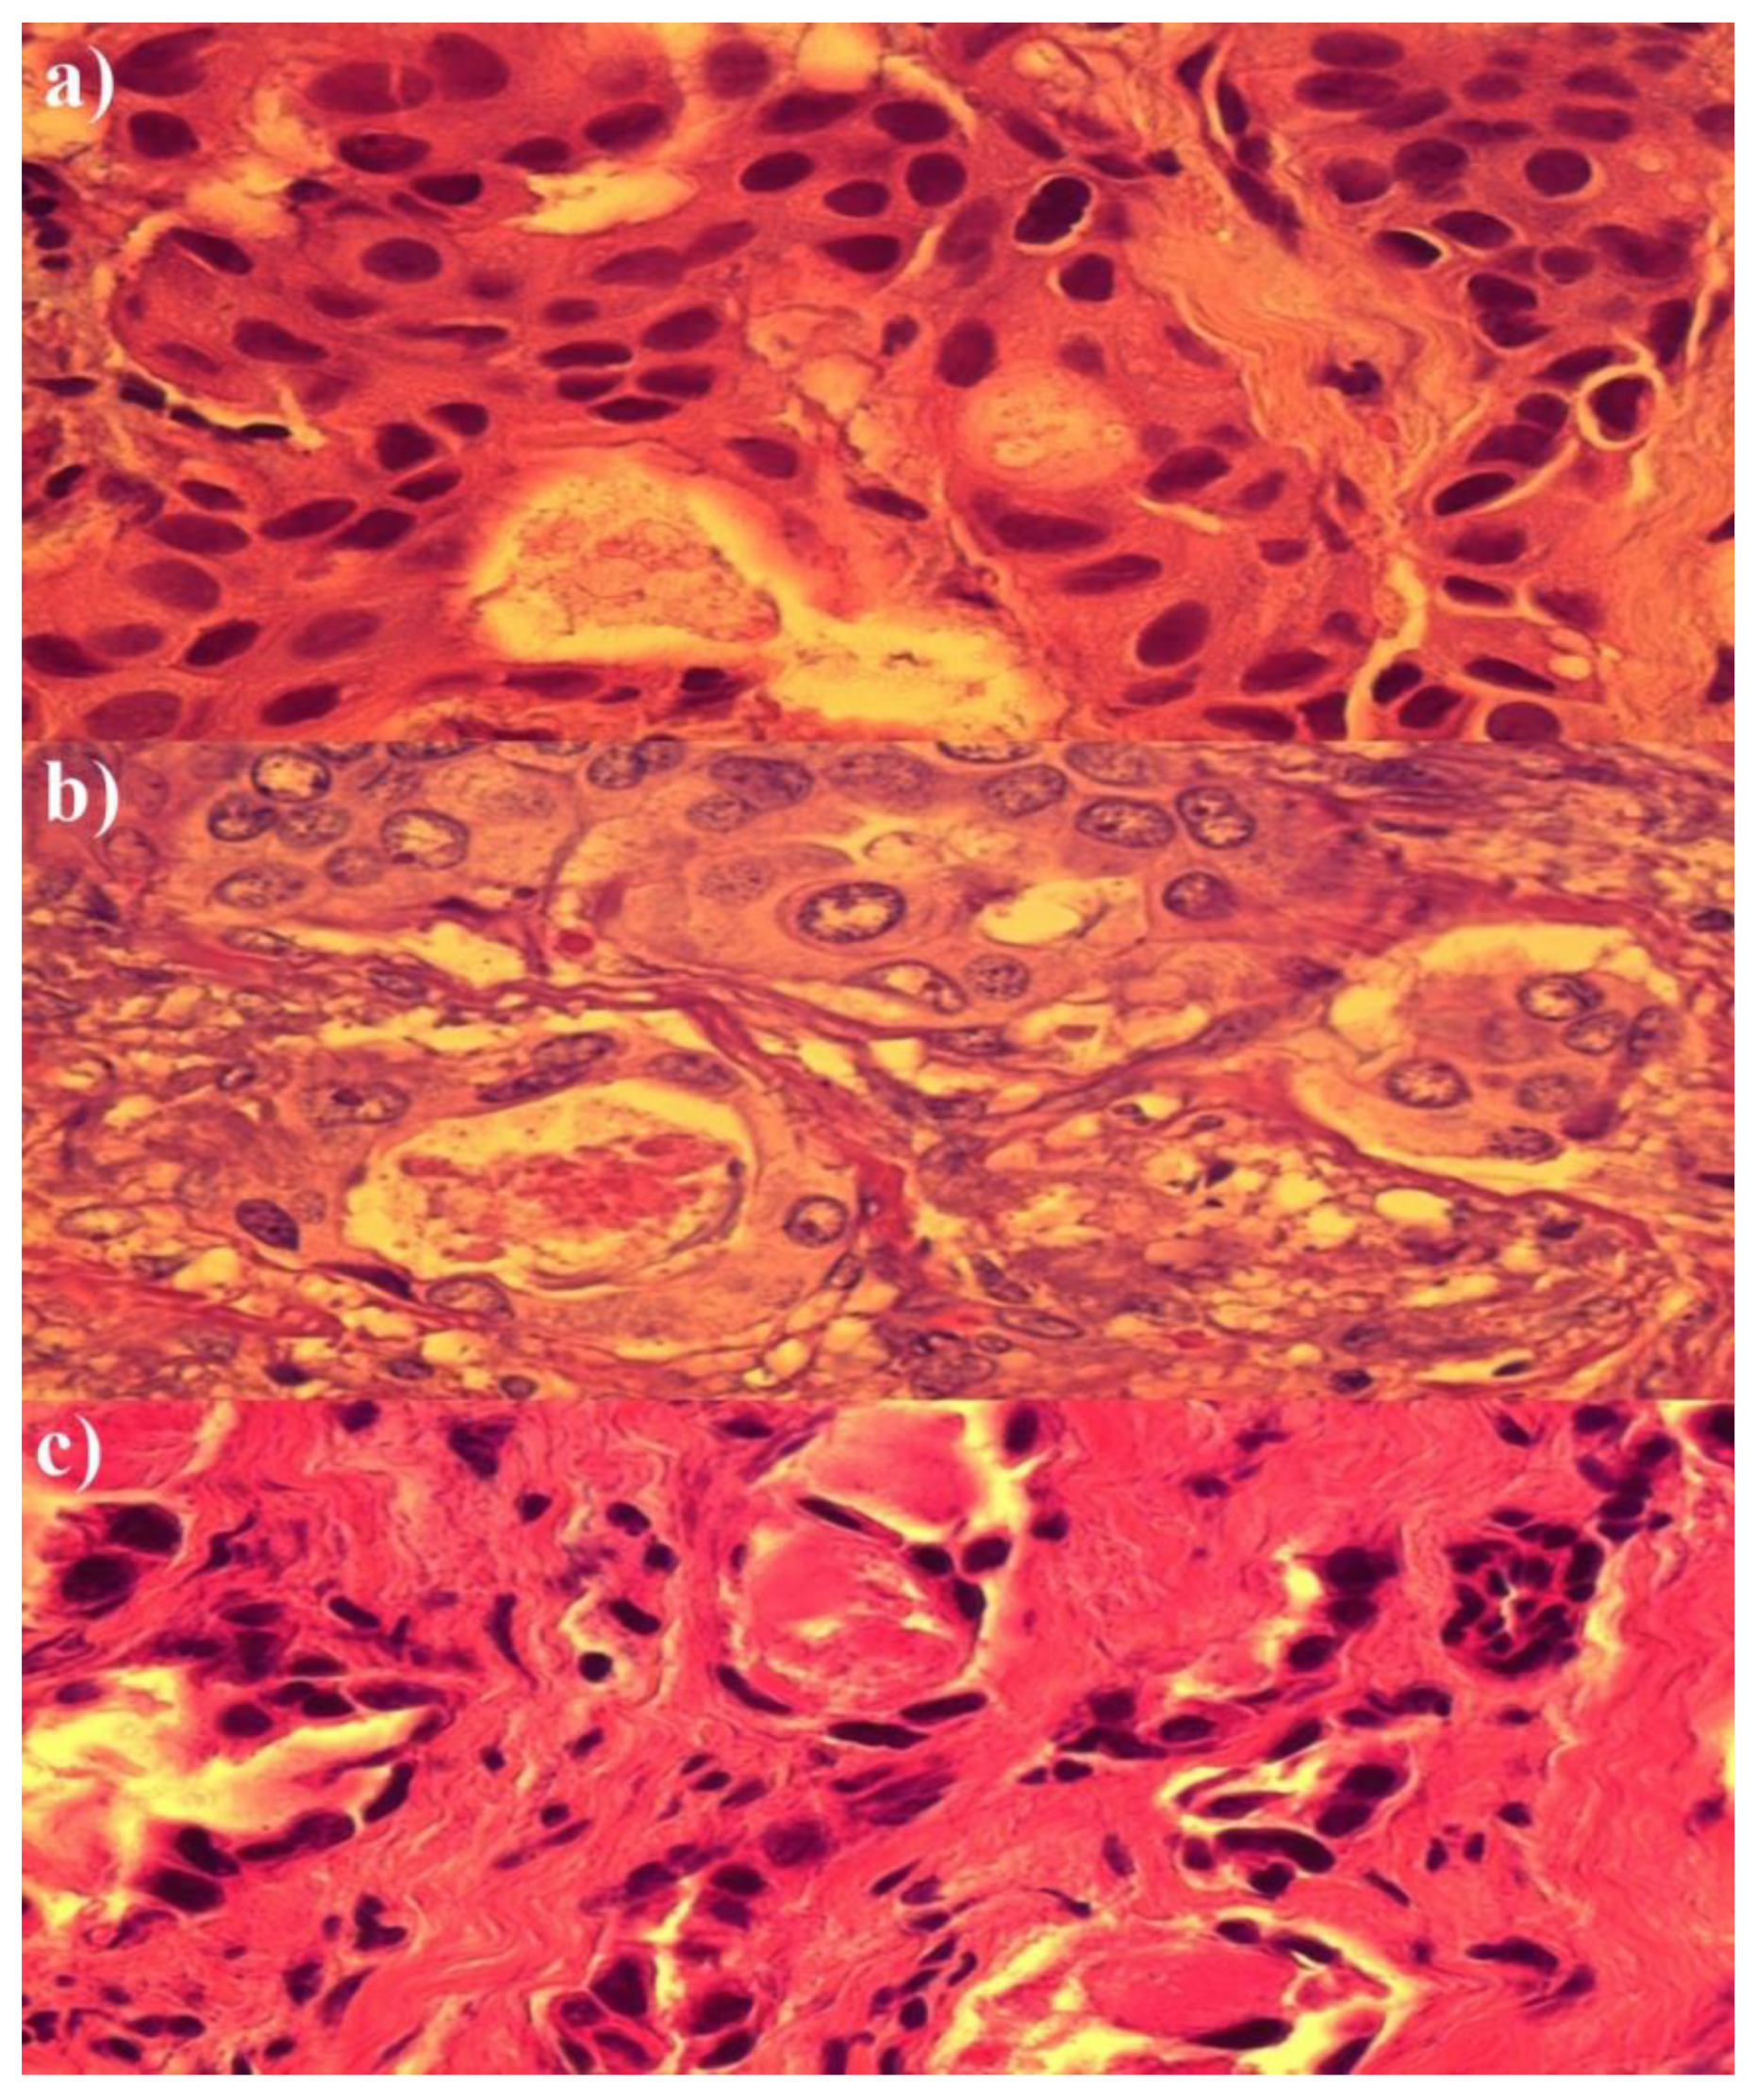

Histopathological Analysis of the Effect of Photodynamic Action on Post-Chemotherapy Excised Breast Cancer Tissue

3. Results